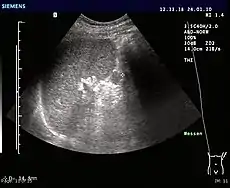

- Ultrasonography of an accessory spleen.